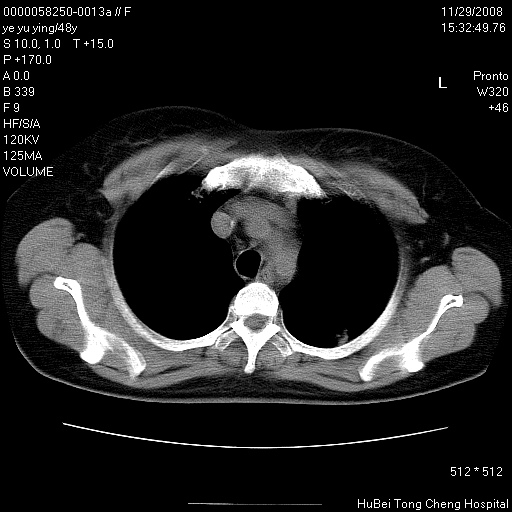

以下是引用zsl6918在2008-11-29 21:47:00的发言:[br]恶性肿瘤病史,转移瘤首先考虑。脂肪肝,胆囊结石。

以下是引用huenhao在2008-11-29 22:11:00的发言:[br]脂肪肝,胆囊结石。左肺病灶建议定期复查。

以下是引用liuyue在2008-11-30 5:44:00的发言:[br]1.左肺病变,首先考虑感染性病变,转移待排;建议治疗后复查。[br]2.肝脏密度普遍减低,考虑与化疗有关。[br]3.胆囊结石.